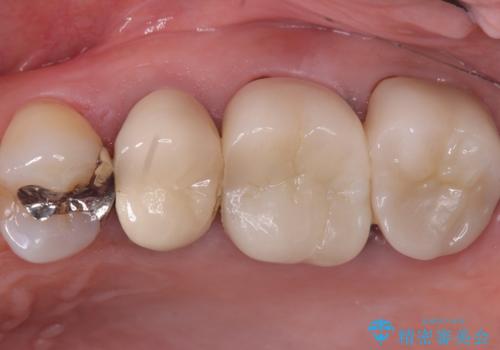

【セラミッククラウン】土台と被せものがズレている気がする

- 主訴:いつも物が詰まる場所があり気になる。衛生士に被せものと土台の境目に汚れが溜まっている箇所があると指摘され気になっている。

過去に入れた被せものと土台の歯との適合が悪く、隙間が出来ておりそこに汚れが溜まりやすい状態になっていました。セラミッククラウンでのやり替えとなりました。

唇側マージン不適なこと説明し、審美性・適合性に優れたセラミッククラウン(スタンダード)でのやり替えとなりました。